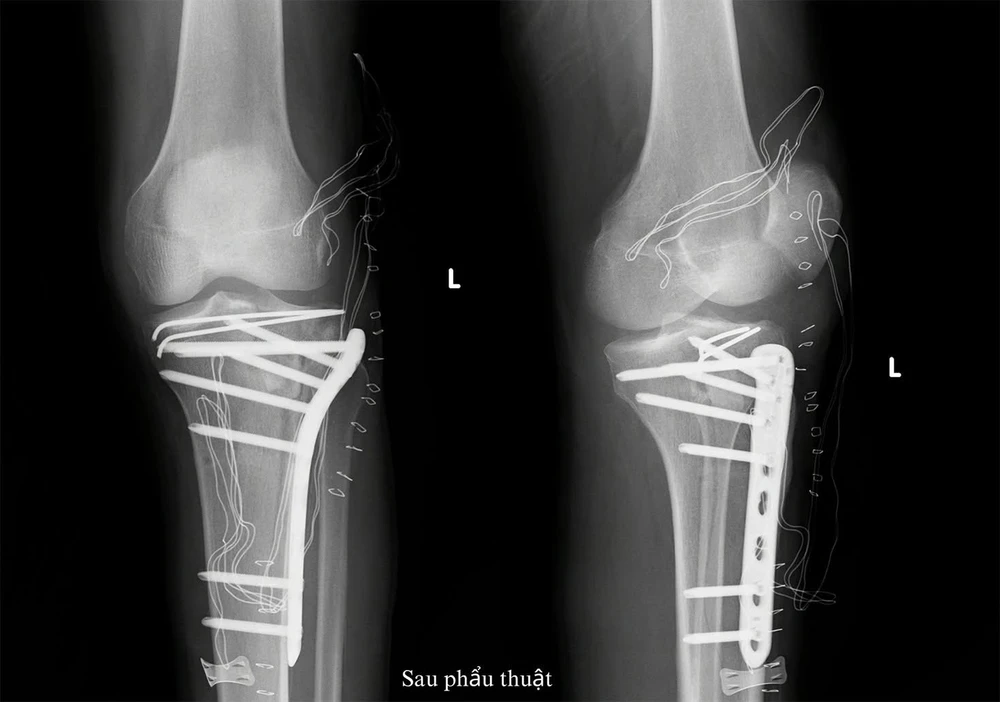

Hình ảnh chẩn đoán gãy mâm chày sau phẫu thuật. Ảnh: BVCC

“Chúng tôi phải đục bỏ phần cal thì mới có thể nâng được mảnh gãy kèm mặt khớp mâm chày lên. Sau khi nâng mảnh gãy mặt khớp thì xương có ổ khuyết hổng lớn, cần được ghép xương tự thân để lấp đầy ổ khuyết hổng”, BS Tài thông tin.

Sau phẫu thuật, bệnh nhân được chăm sóc tích cực với các biện pháp kiểm soát đau đa mô thức, ưu tiên thuốc giảm đau không opioid, rút sớm ống thông và dẫn lưu để hạn chế nguy cơ nhiễm trùng. Bệnh nhân cũng được bổ sung dinh dưỡng sớm qua đường miệng và được hướng dẫn vận động sớm để phòng ngừa huyết khối.

Hiện, sức khỏe bệnh nhân đang hồi phục tốt, đang được hướng dẫn tập vật lý trị liệu để phục hồi chức năng vận động và dự kiến xuất viện trong 2-3 ngày tới.